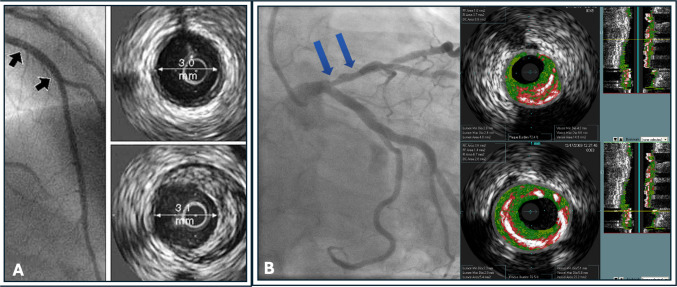

回顾的目的:我们试图回顾各种冠状动脉内成像方式(血管内超声、光学相干断层扫描和近红外光谱)以及支持其在临床实践中应用的最新证据。最近的发现:越来越多的证据表明,在改善经皮冠状动脉介入治疗(PCI)的结果方面,成像引导策略优于单独的血管造影术。一个有趣的和有前途的应用是使用这些设备来识别和治疗高风险或易损斑块。这些模式的应用在特殊的临床情况也进行了审查。血管内成像提供了血管造影以外的信息,可用于改善PCI患者的预后。新出现的证据已被纳入最新的实践指南建议。未来的研究正在进行中,以确定血管内成像对易损斑块的检测和治疗的益处。

Recent findings: There is an increasing body of evidence that demonstrates that imaging-guided strategies are superior to angiography alone to improve outcomes of percutaneous coronary intervention (PCI). An intriguing and promising application is use of these devices to identify and treat high-risk or vulnerable plaques. The application of these modalities in special clinical scenarios is also reviewed. Intravascular imaging provides information beyond the angiogram that can be used to improve patient outcomes during PCI. The emerging evidence has been incorporated into the most recent practice Guideline recommendations. Future research is underway to establish the benefit of intravascular imaging for detection and treatment of vulnerable plaques.